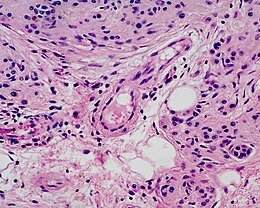

Un nævus congénital mélanocytaire est une tumeur bénigne. Il est composé d’une très grande collection de cellules pigmentaires (mélanocytes) dans une zone délimitée de la peau. Les mélanocytes ont comme origine embryologique la crête neurale[1]. Ces cellules migrent vers la peau et colonisent à peu près tous les tissus du corps[2].